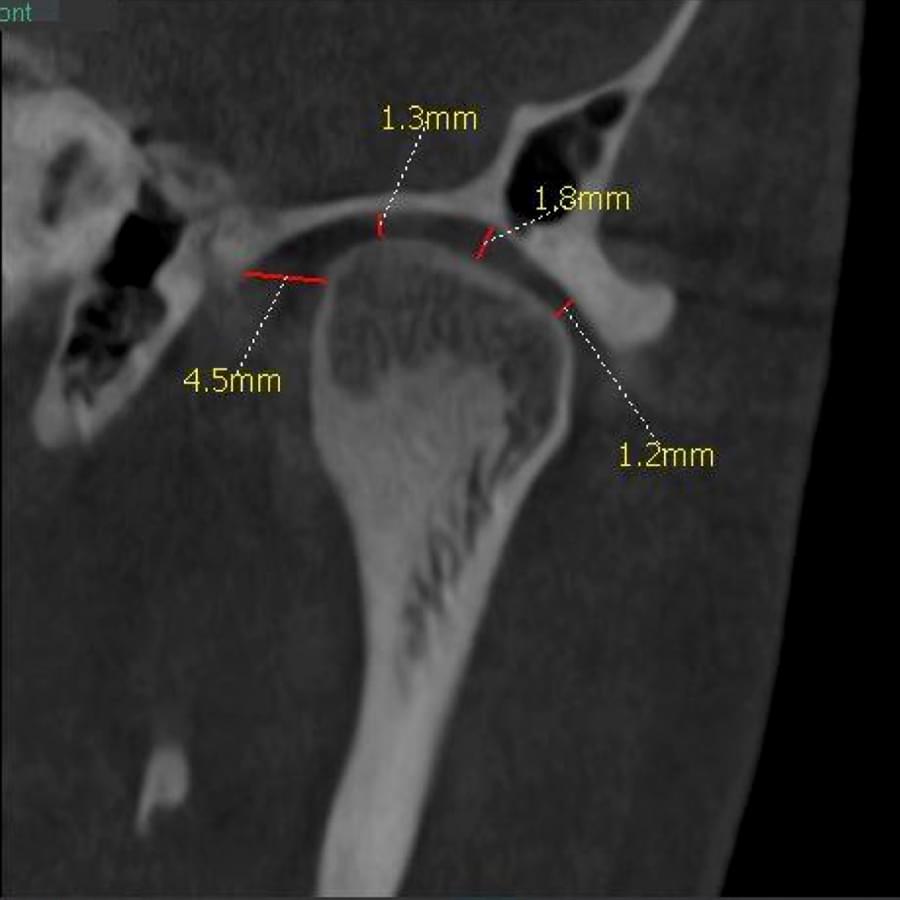

3D цефалометричний аналіз є сучасною технологією, яка дозволяє отримувати точніші,

комплексніші та надійніші дані про зубну та скелетну структуру. Ця технологія може стати

великим кроком в перед для ортодонтів, які хочуть забезпечити найкраще можливе лікування

своїх пацієнтів.

Основні переваги 3D цефалометричного аналізу:

Точність: 3D цефалометричний аналіз забезпечує точніше визначення розмірів та відстаней між

зубами та кістковими структурами.

Комплексність: ця технологія дозволяє отримувати детальні дані про різні структури, такі як

кістка та м'язи, що дозволяє ортодонтам докладніше досліджувати деякі патології та планувати

лікування.

Надійність: 3D цефалометричний аналіз дозволяє отримувати надійніші результати, оскільки

виключає можливість помилок, пов'язаних зі спотворенням або перекриттям зображень.